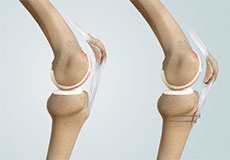

The joint surface is covered by a smooth articular surface that allows pain-free movement in the joint. Arthritis is a general term covering numerous conditions where the joint surface or cartilage wears out. This surface can wear out for several reasons; often the definite cause is not known. Arthritis often affects the knee joint.

Osteoarthritis also called degenerative joint disease, is the most common form of arthritis. It occurs most often in older people. This disease affects the tissue covering the ends of bones in a joint (cartilage).In a person with osteoarthritis, the cartilage becomes damaged and worn out causing pain, swelling, stiffness and restricted movement in the affected joint.